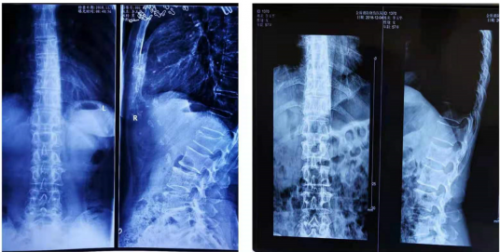

李某某,女,57岁,2018年11月13日,牡丹江市金盾医院DR报告,腰椎第- -节压缩性骨折,经黄静湖中医正骨施“拉伸反折复位法”手法复位,口服外敷自制中药,治疗21天后患处复位稳定。